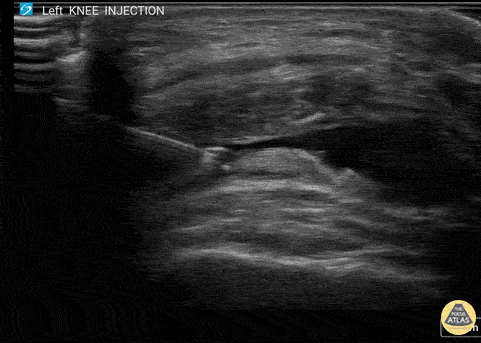

60 y/o F with knee arthritis getting corticosteroid joint injection in left suprapatellar recess. Ultrasound probe in transverse axis just superior to the patella. Needle approach lateral to medial. Infiltrate seen injected into anechoic suprapatellar recess. The suprapatellar recess is continuous with the tibiofemoral joint. Deep to suprapellar recess in this video is the prefemoral fat pad. Just superior to the suprapatellar recess in this image is the quadriceps tendon in short axis appearing as a fibrillar structure. Contributors: Eben Alexander, DO Devesh Patel, MD Eastern Virginia Medical School